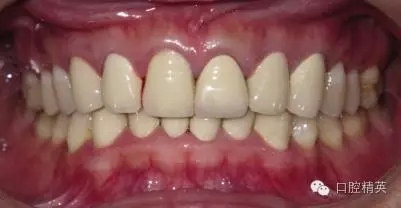

修復(fù),尤其是前牙美觀修復(fù),充分有效的醫(yī)患溝通非常必要。修復(fù)前,要充分了解患者的想法,美觀修復(fù)的目的或目標(biāo)是什么,在對患者進(jìn)行了常規(guī)檢查和溝通后,對患者情況進(jìn)行一個(gè)客觀的分析,根據(jù)患者的情況和自己的技術(shù)條件對能否滿足患者的要求作出判斷。基于對患者的充分了解,提出合理可行的治療方案,包括材料與價(jià)格,并得到患者的理解與配合,為接下來的治療鋪平道路。術(shù)前常規(guī)取研究模,拍X 光片和數(shù)碼照片,盡量多的保留原始資料。必要時(shí)進(jìn)行蠟型的制作及簽署術(shù)前治療同意書。

關(guān)于基礎(chǔ)治療。牙周治療和根管治療是美觀修復(fù)的基礎(chǔ)。根據(jù)術(shù)前檢查,常規(guī)先行全口潔治,必要時(shí)局部深層次的牙周治療,待牙周情況穩(wěn)定后,再考慮牙體預(yù)備與取模(見圖1、2)。在牙周炎未控制或牙齦紅腫的情況下,是不可能預(yù)備好牙齒,不可能取得清晰的印模,更談不上成功的美觀修復(fù)。

LAVA 全瓷冠強(qiáng)度高,顏色自然,邊緣高度密合,切端可見半透明感,整體效果理想,與修復(fù)前(見圖1)相比取得了醫(yī)患均滿意的效果。